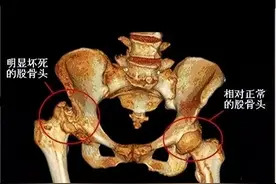

股骨头坏死(Avascular Necrosis of the Femoral Head,AVN)是一种股骨头因血液供应中断导致骨组织死亡的疾病,是骨坏死大类中的一种比较常见的病症。早期症状包括髋部隐痛、活动受限,后期可能引发股骨头塌陷、骨关节炎甚至残疾。